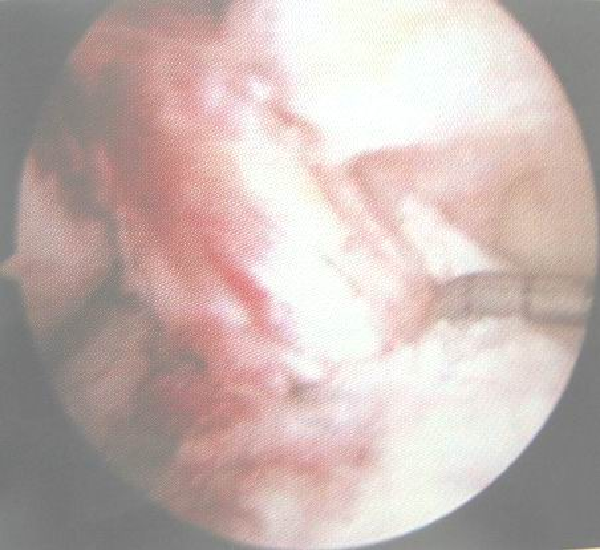

正常前交叉韧带

前交叉韧带损伤后形成的疤痕组织

关节镜下观